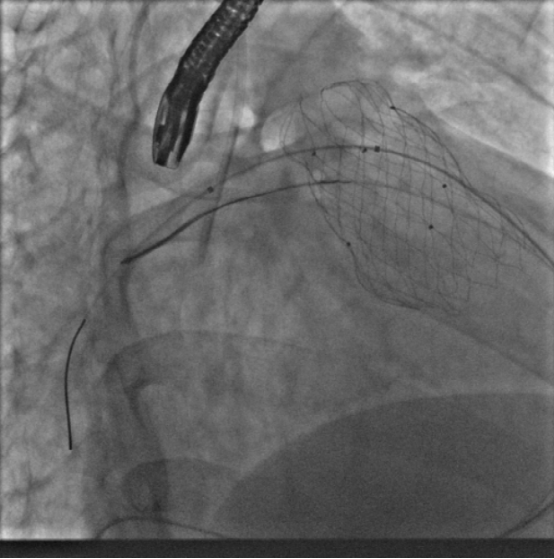

10月10日,葛均波院士、周达新教授团队转播了一台高难度的经导管肺动脉瓣置换术(PPVI),患者为法洛四联症纠治术并发肺动脉瓣反流患者。为防止患者右心功能障碍进一步恶化,团队决定为其行PPVI。术中考虑到患者肺动脉分叉较短,存在瓣膜释放后移位风险,故选择高位释放法。但释放瓣膜后造影提示右肺动脉开口局部被阻挡。

在先后尝试Snare圈套瓣架下缘下拉法、双导管圈套瓣架上缘下拉法,但效果不理想。团队迅速调整方案,创新性的采用Snare圈套住主路的Lunder quist导丝,建立球囊输送轨道,

如此球囊顺利通过瓣膜支架网孔进入右肺动脉,在DSA指引下逐步扩张球囊,成功使人工瓣膜支架向右心室侧移位。复查造影提示右肺动脉开口未见明显阻挡,跨右肺动脉压差小于8mmHg。复查肺动脉主干造影,显示人工瓣膜启闭良好,轻微瓣膜反流。最终手术疗效显著、取得令人满意的结果。肺瓣植入阻挡肺动脉是少见并发症,本例采用了多种技术,最终完美解决问题,为此类病人处理提供了很好经验参考。